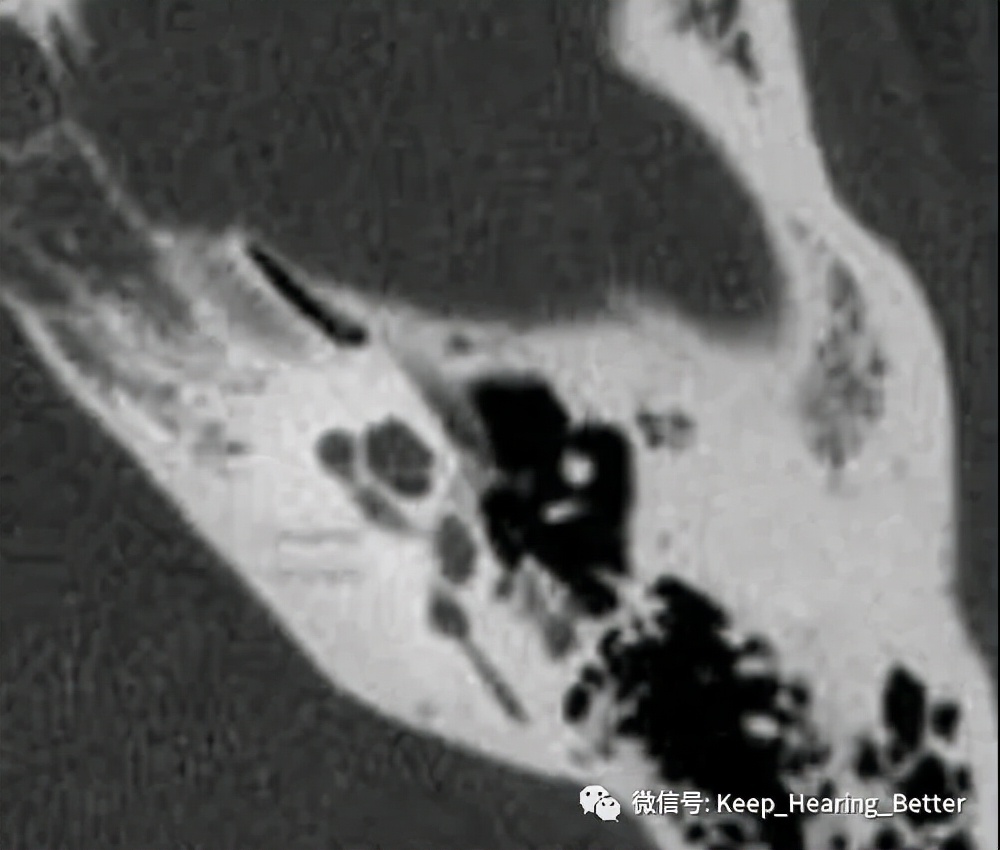

治疗:手术,即人工镫骨(Piston)植入术

患者左耳人工镫骨植入术后18个月复查听力结果